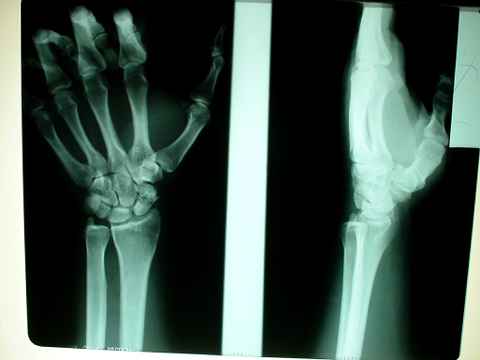

Recibimos en nuestra enfermería al final del último toro a este joven picador que manifiesta dolencias agudas en su muñeca derecha.

Después de picar su toro este se resbala con la pica puesta y la muñeca se resiente al distenderse. Esto podría ser una simple distensión o esguince de esta articulación. Sin embargo a la exploración notamos que el dolor agudo se refiere a la zona profunda en dirección al hueso escafoides.

Citamos al paciente al día siguiente para hacerle un estudio radiológico.

Nuestro primer diagnóstico fue: Probable Fisura del hueso calcáneo. Como de costumbre pusimos tratamiento médico, postural, inmovilización en postura adecuada con vendaje y crío terapia.

Y nos llevamos una sorpresa nada ver la placa...

El hueso escafoides está partido por la mitad y además tiene zonas de necrosis ósea e incluso una excrescencia ósea tipo espinoso en el fragmento distal.

Esto quería decir que este señor tuvo una fractura antigua. Que según la anamnesis se produjo hace tres años y desde entonces viene toreando y reiteradamente volviendo a partirse en dos el hueso; si es que alguna vez se soldó.

Lesión típica de los picadores. Hueso que ya no puede soldar y sólo nos queda el recurso de intervenir si las molestias lo ameritan y colocar algún tipo de fijación.

De momento baja por accidente laboral. Inmovilización por 10 días y revisión de evolución.

Pronóstico menos grave.